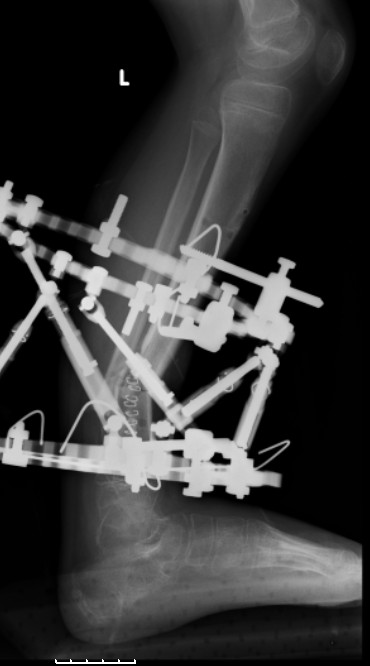

Re: case tibial defect

Another choice is simply perform shortening + posterior angulation with Ilizarov or TSF , than gradual correction of the angulation.After all apply third ring on the proximal tibia and start lengthening.

We had recently similar case in 14 years old boy with 45 mm bone defect after open tibial fracture.Boy doing excellent .This technique is not new, Sasha Lerner did it in Rambam , Rozbruch wrote also.

Another advantage of this techniqe is relaxation of soft tissue and possibility for closure even large defects of the skin.In your case I will apply ring on the foot and mid diaphysis of the tibia ,removal of the fibular plate,sindesmotic wire, and after correction of angulation on the proximal tibia.